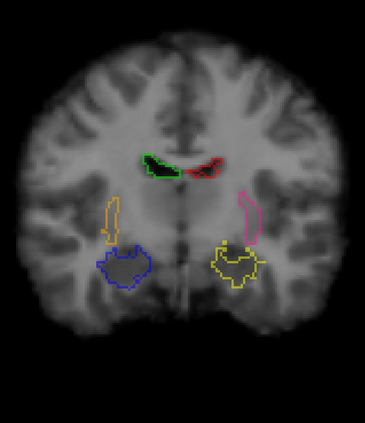

Medical image registration is a fundamental and critical task in medical image analysis. With the rapid development of deep learning, convolutional neural networks (CNN) have dominated the medical image registration field. Due to the disadvantage of the local receptive field of CNN, some recent registration methods have focused on using transformers for non-local registration. However, the standard Transformer has a vast number of parameters and high computational complexity, which causes Transformer can only be applied at the bottom of the registration models. As a result, only coarse information is available at the lowest resolution, limiting the contribution of Transformer in their models. To address these challenges, we propose a convolution-based efficient multi-head self-attention (CEMSA) block, which reduces the parameters of the traditional Transformer and captures local spatial context information for reducing semantic ambiguity in the attention mechanism. Based on the proposed CEMSA, we present a novel Symmetric Transformer-based model (SymTrans). SymTrans employs the Transformer blocks in the encoder and the decoder respectively to model the long-range spatial cross-image relevance. We apply SymTrans to the displacement field and diffeomorphic registration. Experimental results show that our proposed method achieves state-of-the-art performance in image registration. Our code is publicly available at \url{https://github.com/MingR-Ma/SymTrans}.